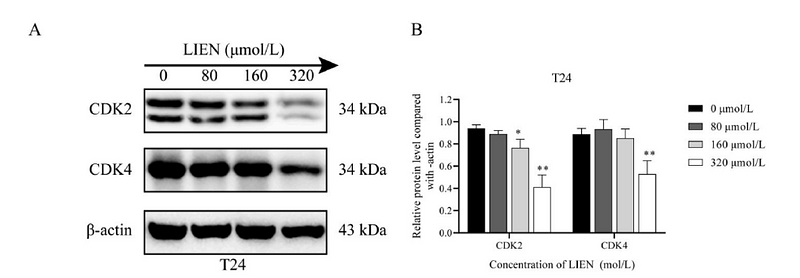

CDK2 and CDK4 targeted liensinine inhibits the growth of bladder cancer T24 cells

Author:

PMID: 37423554

期刊: Chemico-Biological Interactions

应用: WB

反应种属: Human

发表时间: 2023 Jul